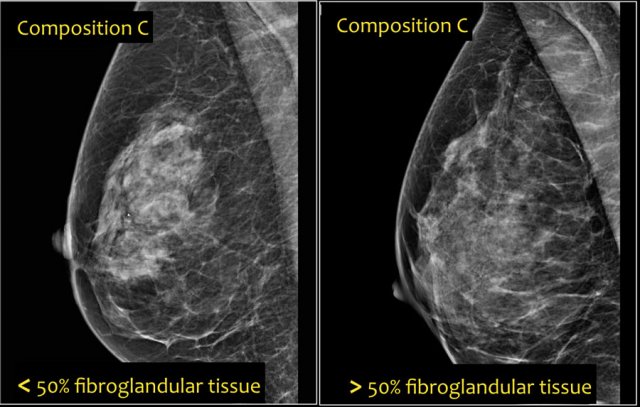

In the BI-RADS edition 2003 the assignment of the breast composition was based on the overall density resulting in ACR catergory 1 ( <25% fibroglandular tissue), category 2 ( 25-50%), category 3 (50-75%) and category 4 (>75%).

In BI-RADS 2013 the use of percentages is discouraged, because in individual cases it is more important to take into account the chance that a mass can be obscured by fibroglandular tissue than the percentage of breast density as an indicator for breast cancer risk.

In the BI-RADS edition 2013 the assignment of the breast composition is changed into a, b, c and d-categories followed by a description:

• a- The breast are almost entirely fatty.

Mammography is highly sensitive in this setting.

• b- There are scattered areas of fibroglandular density.

The term density describes the degree of x-ray attenuation of breast tissue but not discrete mammographic findings.

• c- The breasts are heterogeneously dense, which may obscure small masses.

Some areas in the breasts are sufficiently dense to obscure small masses.

• d - The breasts are extremely dense, which lowers the sensitivity of mammography.

Notice in the left example the composition is c - heterogeneously dense, although the volume of fibroglandular tissue is less than 50%.

The fibroglandular tissue in the upper part is sufficiently dense to obscure small masses.

So it is called c, because small masses can be obscured.

Historically this would have been called an ACR 2: 25-50% density.

The example on the right has more than 50% glandular tissue and is also called composition c.